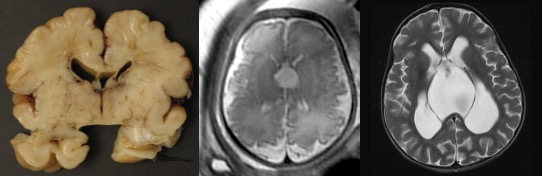

la malformation de Dandy-Walker

il s’agit d’une malformation due à l’imperforation de la toile choroïdienne du V4, qui soulève de façon caractéristique le vermis cérébelleux.

le pronostic est incertain ; les éléments de pronostic défavorable sont :

- l’existence d’une hydrocéphalie évolutive, avec dilatation ventriculaire et tronc cérébral plaqué en avant

- l’hypoplasie du cervelet

- le contexte malformatif (syndrome PHACE)